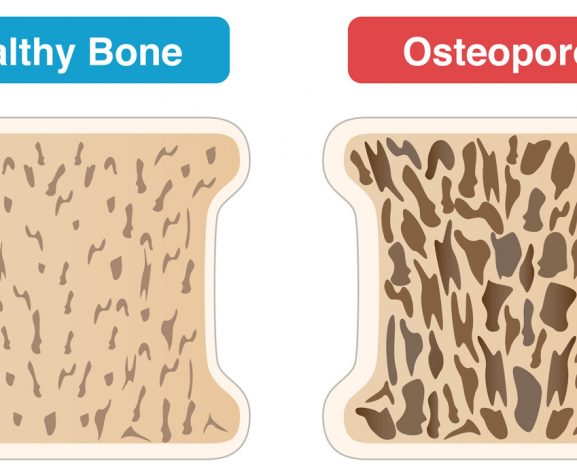

Osteoporosis